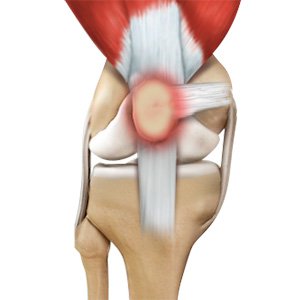

Patellar Tendinitis

Patellar tendinitis, also known as "jumper's knee", is an inflammation of the patellar tendon that connects your kneecap (patella) to your shinbone. This tendon helps in extension of the lower leg.

Jumper's Knee

Jumper’s knee, also known as patellar tendinitis, is inflammation of the patellar tendon that connects your kneecap (patella) to your shinbone. This tendon helps in the extension of the lower leg.